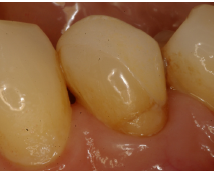

Al momento del examen, 10 (90.9%) EC estaban en función en 10 pacientes. Un molar 26, restaurado con EC, se perdió por enfermedad periodontal después de 12 años y 9 meses en función. Ninguna restauración se desprendió, no hubo recidiva de caries y al examen radiográfico no se observaron lesiones patológicas en los 10 DPET en función (Figs. 1a,1d; 2c; 3c,3d; 4c).

Preparación dentaria en #36 para EC. Un chamfer fue realizado en la pared vestibular.

EC en #36 después de 18 años (IPS-Empress). Obsérvense las facetas de desgaste parafuncionales, la recesión gingival y la lesión cervical no-cariosa. Esta paciente se negó a usar placa de estabilización nocturna.